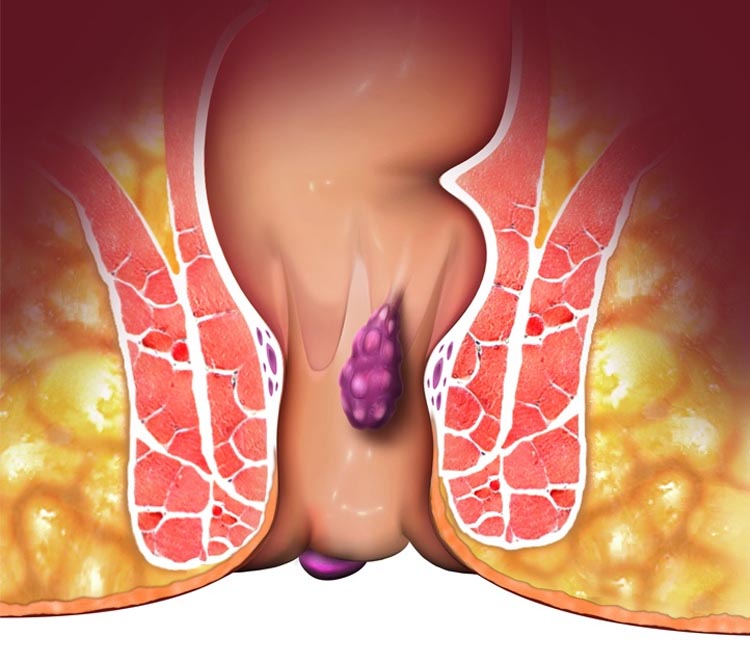

We specialize in advanced hemorrhoid treatments, using the latest surgical techniques for effective relief from discomfort, pain, and bleeding, ensuring a faster recovery with minimal downtime.